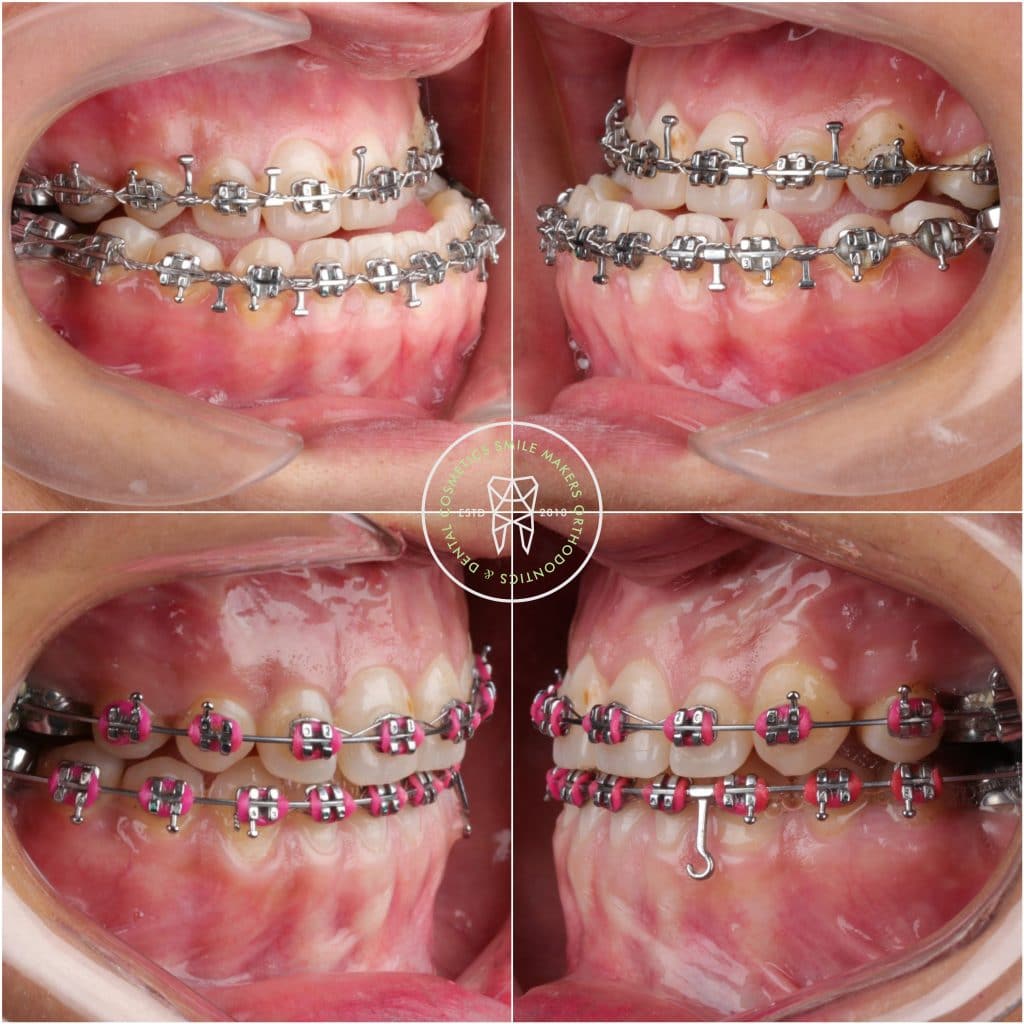

- A . Orthodontic preparation : including extraction of UL 4 , leveling and alignment , decompensation , arch coordination , creating surgical wafers for bimaxillary surgery and referred to the surgeon

* complication : the case dismissed after surgery without instructions to keep using the wafer along with elastics , also multiple debondings happened during the surgery , so patient came to me 3 weeks after surgery with posterior openbite , progressing shift of lower midline towards the right side , and cl III canines in left side

*managment : intermaxillary elastics , and unilateral buccal shelf TAD inserted in left side to distalize this segment to obtain cl I canine , and coincident midline .